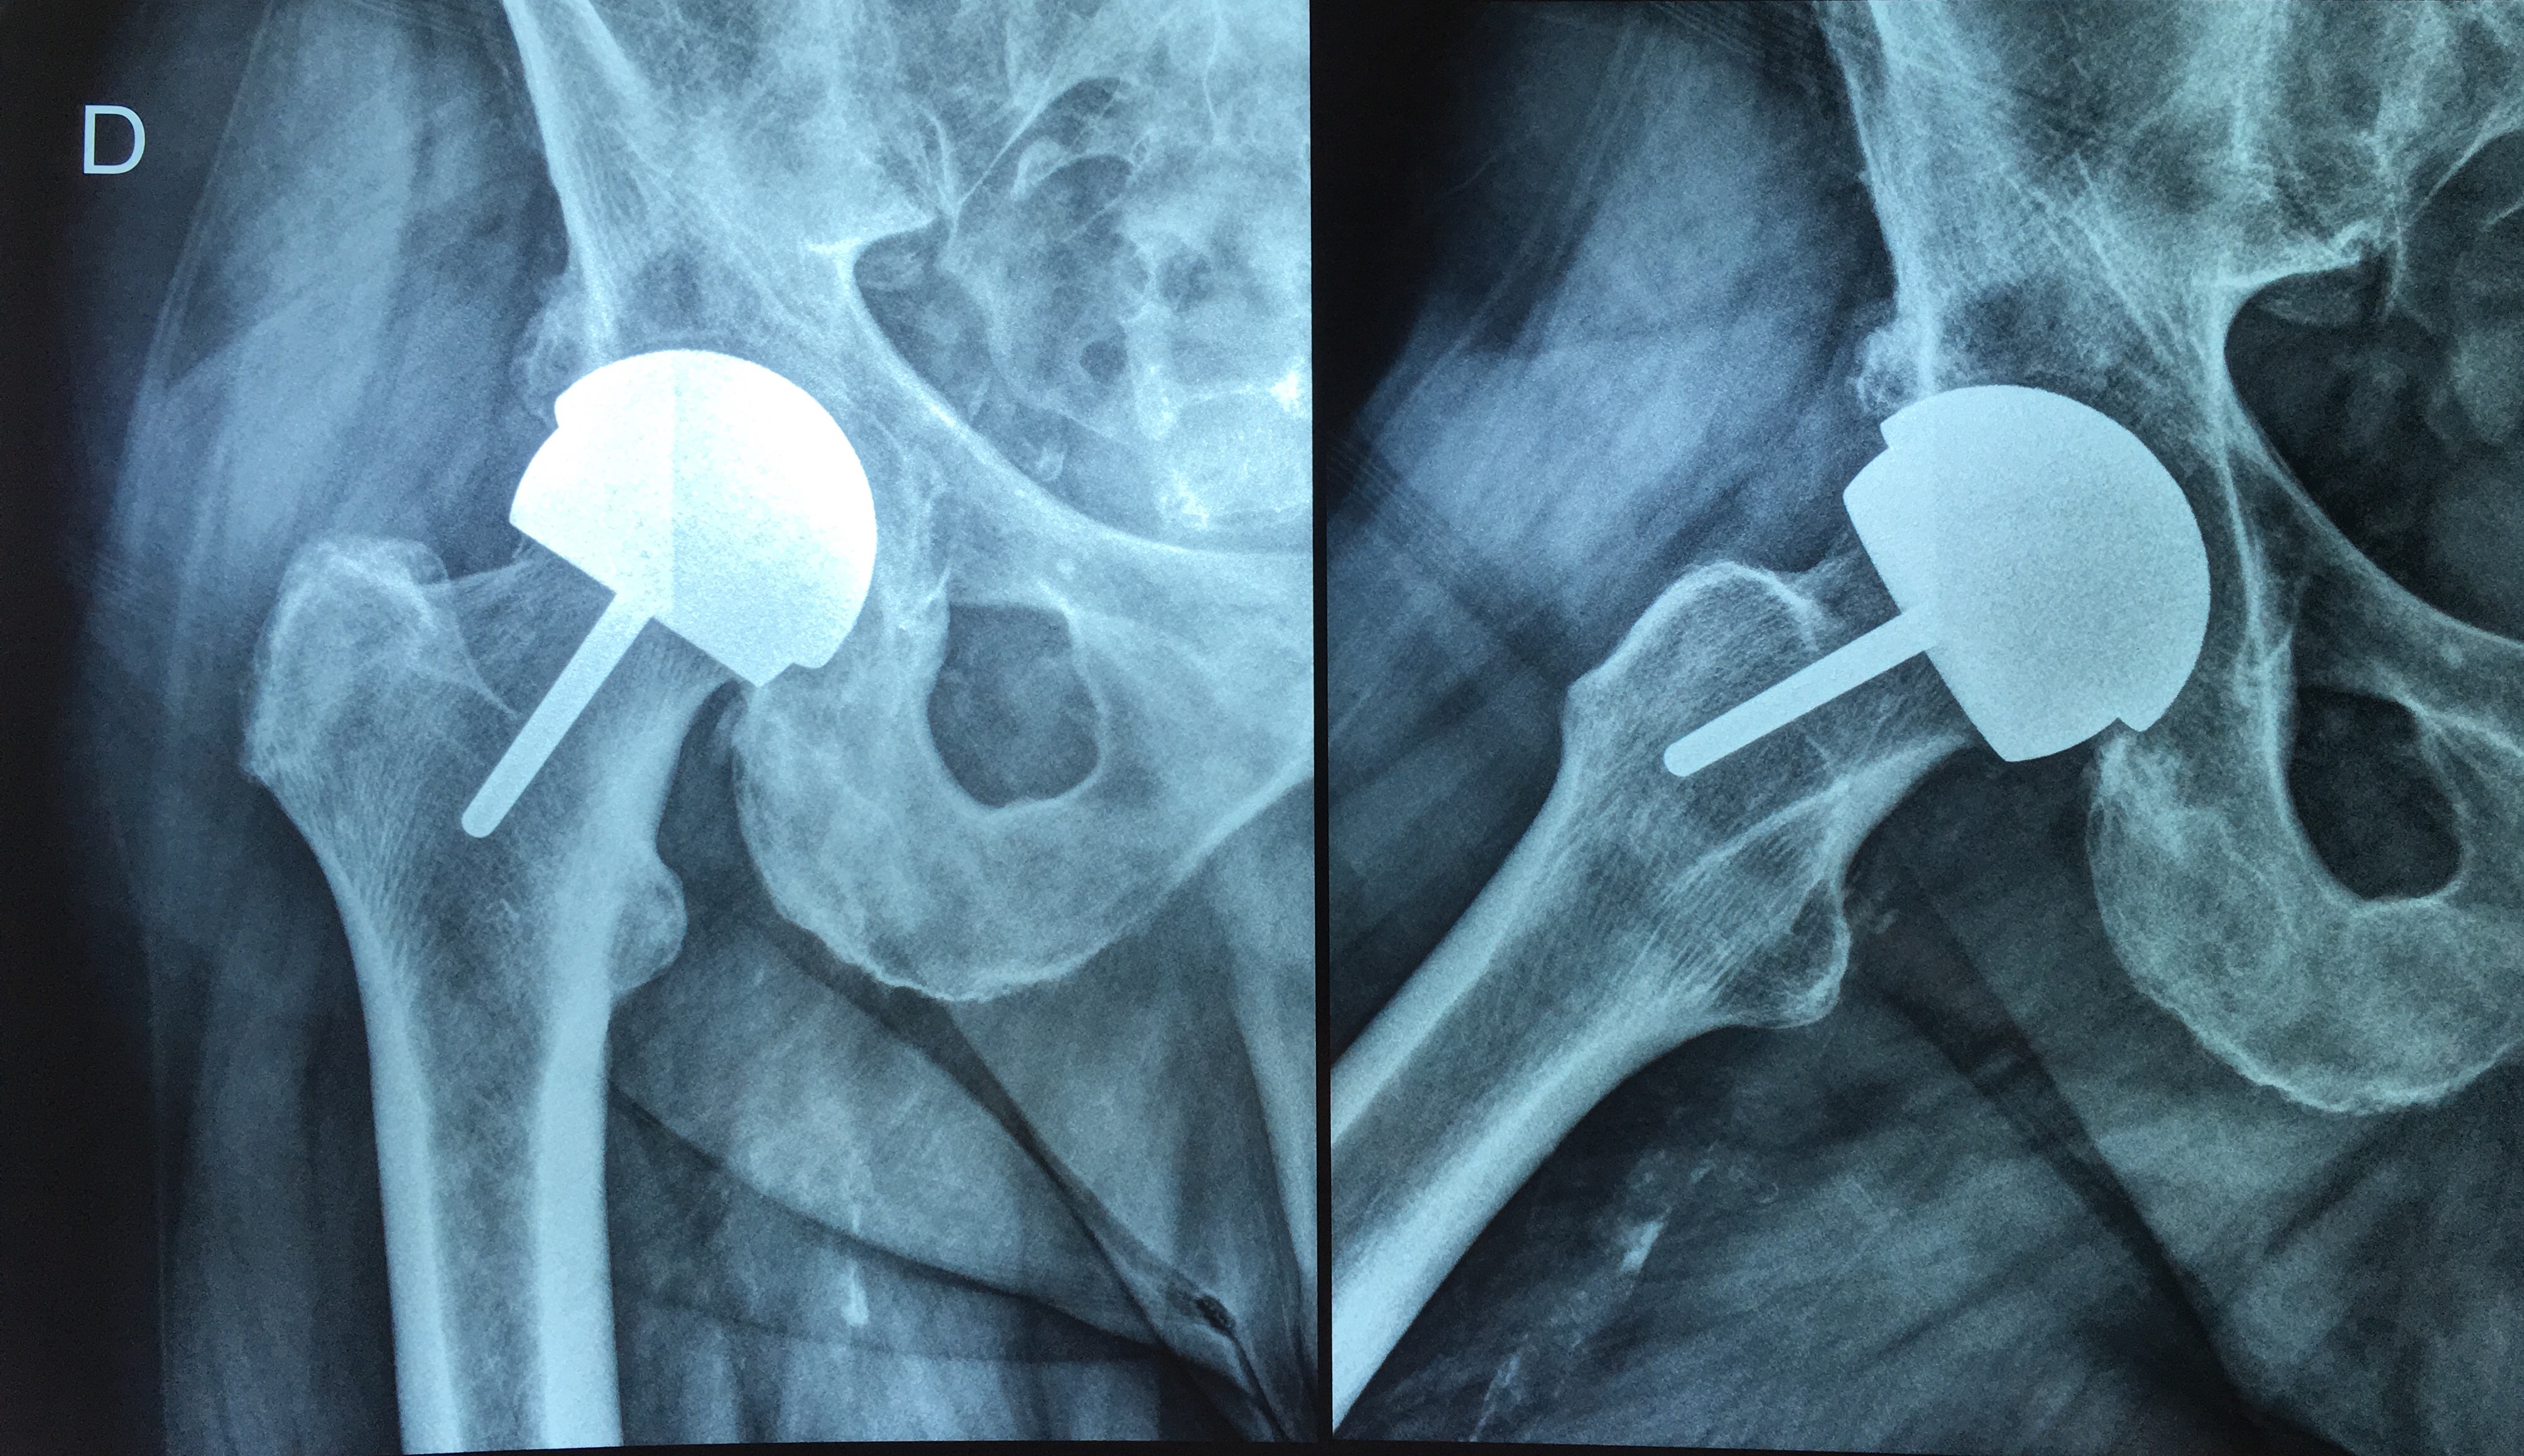

Cotilos de doble movilidad. Uso para la revisión femoral aislada de prótesis de cadera con fricción metal/metal con cabezas grandes. [Use of dual mobility acetabular cups for isolated femoral revision of metal on metal hip resurfacing arthroplasty using larger femoral heads]